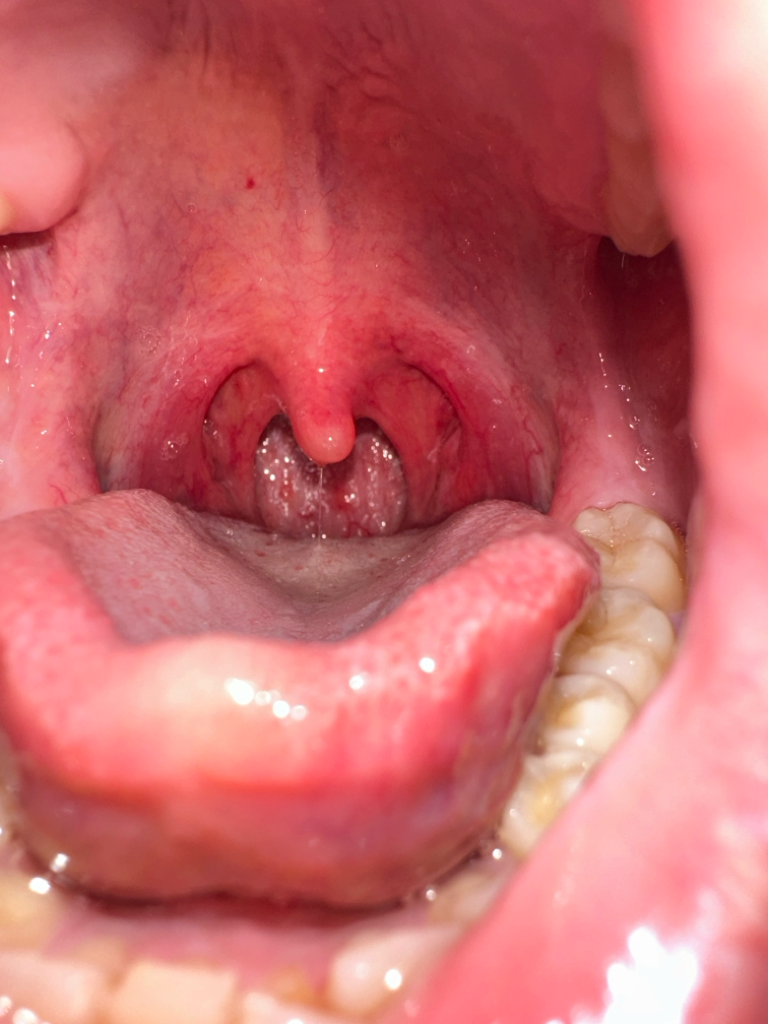

목이 너무 아파요 항생제를 3일 동안 먹고 있는데 차도는 없고 침을 안삼켜도 통증이 있습니다. 물도 미지근하게 계속 먹지만 별 차도가 없습니다 목감기가 아닌 것 같아서 증상이 뭔지 알 수 있을까요

• 1번 째 사진

일단 사진으로 보이는 부분에는 큰 이상은 없습니다

하지만 실제로 보는 것과 다를 수 있으니

목통증이 심하시면 이비인후과 진료를 받아보시기 바랍니다

인후쪽은 인후염증 (Pharyngeal injection) 이 있으신 것으로 보입니다 . 인후염이 동반된 상기도 감염의 전형적인 소견입니다.